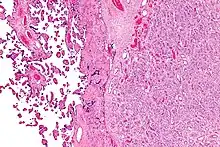

| Placenta with an especially large 10cm chorioangioma | |

The origin of chorioangioma is from primitive chorionic mesenchyme. It develops when the blood vessels and stroma undergo rapid proliferation independent of the surrounding tissue. Based on histological features, chorioangioma is classified by Marchetti[5] into three types:[6]

- Angiomatous (vascular) type : This is the most common type of choriocarcinoma. It is distinguished by the presence of numerous small blood vessels.

Histologically, chorioangiomas consist of abundant vascular channels and may be cellular.